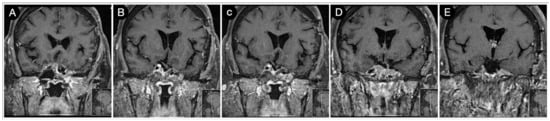

3.3.2. Case #5: Extension beyond the Lateral Wall of the Cavernous Sinus

3.3.3. Case #6: Encasement of the Posterior Communicating and Anterior Choroidal Artery

Case #7: Encasement of the Paraclinoid and Supraclinoid Internal Carotid Artery